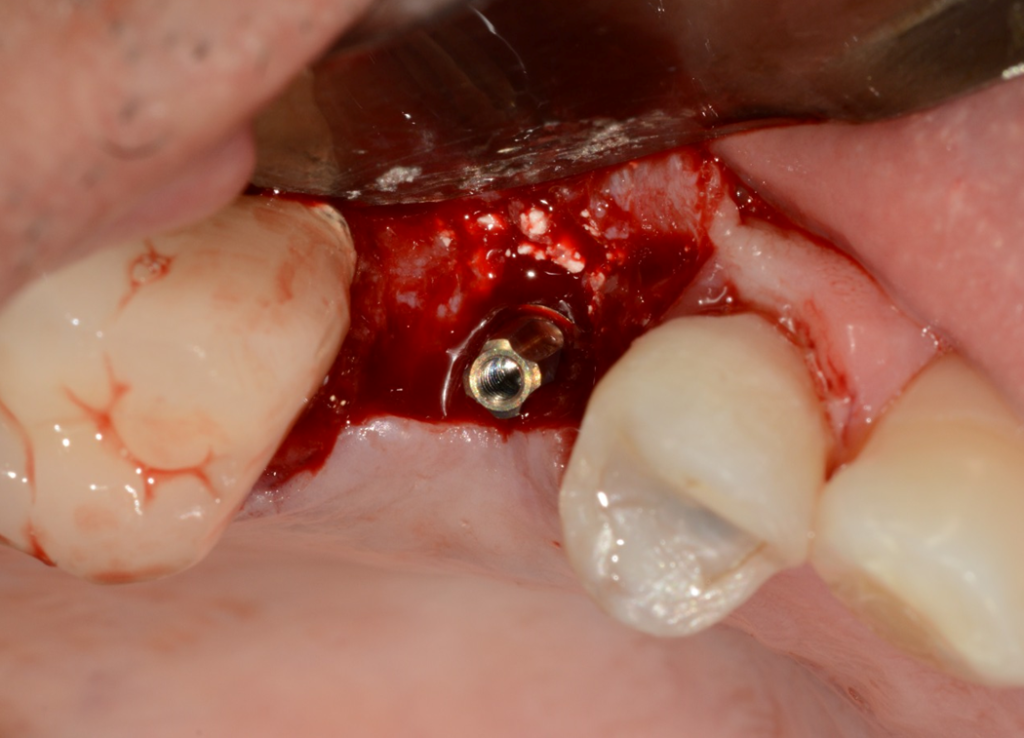

No presente caso, o paciente procurou nossa clínica acreditando que a coroa sobre implante do 15 estava apenas frouxa, e que seria possível resolver apertando o parafuso. Ao exame clínico, apresentava uma coroa cimentada sobre componente UCLA fundida e parafusada diretamente sobre o hexágono do implante (um HE de 3.5 mm de diâmetro e plataforma da mesma medida). Após o corte da coroa para acessar o parafuso, na remoção do conjunto, a plataforma do implante veio anexada à coroa, denotando a fratura do implante, que foi comprovada com radiografia periapical (Figuras 1 e 2). Decidimos por fazer uma prótese adesiva provisória (Figuras 3 e 4) e planejar a remoção do implante com colocação imediata de novo implante, após observado na tomografia cone beam que haveria osso suficiente para isso (Figura 5). O implante foi removido (Figuras 6 e 7) com o uso de broca trefina e fórceps, e um implante Implacil De Bortoli CM Due Cone foi instalado no mesmo momento (Figura 8), com regeneração óssea guiada (ROG) na parede vestibular (Figura 9), que havia ficado muito fina (enxerto ósseo particulado + membrana de colágeno). Apesar de termos obtido bom travamento do implante (45 Ncm), optamos por deixá-lo sem carga pelo período de cinco meses, para respeitar o tempo da ROG (Figuras 10 e 11).